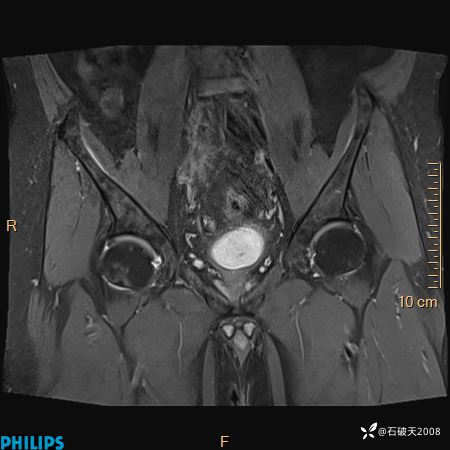

2023年3月份MRI影像

T2压脂冠状位